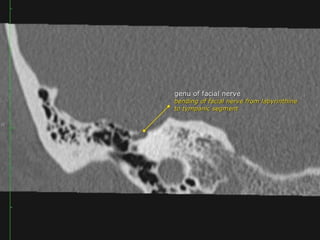

 Intratemporal facial nerv;

CN7 segments: lAC, labyrinthine, tympanic, mastoid segments

Geniculate ganglion = anterior genu

Posterior genu: Tympanic segment bends inferiorly to become mastoid

segment

Segments

 intracranial (cisternal) segment - zero branches

 meatal (canalicular) segment (internal auditory canal): 8 mm long, zero branches

 labyrinthine segment (IAC to geniculate ganglion): 3-4 mm long, 3 branches

(from geniculate ganglion)

 tympanic segment (from geniculate ganglion to pyramidal eminence): 8-11 mm

long, zero branches

 mastoid segment (from pyramidal eminence to stylomastoid foramen): 8-14 mm long, 3

branches

 extratemporal segment (from stylomastoid foramen to division into major branches): 15-

20 mm, 9 branches